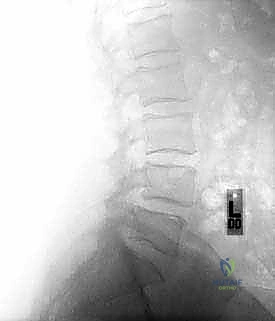

عملية دمج الفقرات (Spinal Fusion) هي إجراء جراحي يهدف إلى ربط فقرتين أو أكثر بشكل دائم، مما يزيل الحركة غير الطبيعية والمؤلمة بينهما، ويعيد الاستقرار الميكانيكي إلى العمود الفقري. في حالتنا هذه، يتم التركيز بشكل خاص على المنطقة الصدرية القطنية (Thoracolumbar Junction)، وهي المنطقة الانتقالية الحرجة التي تربط الجزء العلوي من الظهر (القفص الصدري الصلب) بالجزء السفلي (المنطقة القطنية المتحركة). يتم التثبيت باستخدام أدوات طبية معدنية متطورة (Instrumentation) مثل المسامير السويقية (Pedicle Screws) والقضبان المصنوعة من التيتانيوم.

قبل الخوض في التفاصيل الدقيقة للعملية الجراحية، من الضروري والمهم جداً أن نفهم التشريح المعقد للعمود الفقري الذي نتعامل معه. إن العمود الفقري الصدري القطني هو منطقة انتقالية فريدة من نوعها في جسم الإنسان، حيث تلتقي الفقرات الصدرية (المرتبطة بالضلوع والتي توفر الاستقرار) بالفقرات القطنية (التي تتحمل معظم وزن الجسم وتوفر مدى حركة كبير). هذه المنطقة حيوية ومرنة، ولكنها للأسف أيضاً الأكثر عرضة للإجهاد الميكانيكي، والإصابات الرضية، والكسور.

المنطقة الصدرية القطنية (Thoracolumbar Junction): نقطة الضعف الميكانيكية

هذه المنطقة (من T11 إلى L2) تعتبر نقطة انتقال ميكانيكي حرجة. الجزء الصدري فوقها صلب ومقيد بالقفص الصدري، بينما الجزء القطني تحتها مرن ومتحرك. هذا الانتقال المفاجئ من الصلابة إلى المرونة يجعل هذه المنطقة عرضة بشكل غير متناسب للكسور الرضية (مثل كسور الانفجار بسبب حوادث السيارات أو السقوط من ارتفاع) والإجهاد الميكانيكي الذي يؤدي إلى الانزلاق الفقاري.